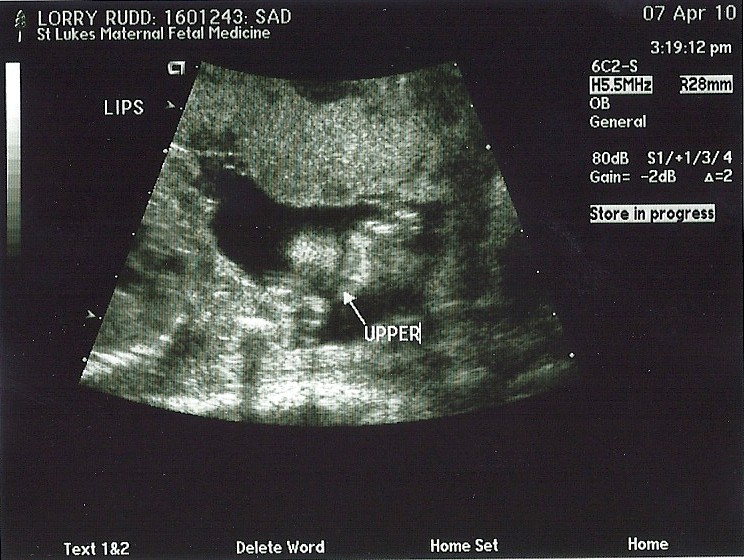

I am teaching in each of the grades, K-5 in their reading class. I teach about an hour in each grade to 5-10 kids and I mostly like it. I just miss my first grade class and wish I could just teach them for the rest of the year! They were very excited to see me and they all thought I was gone the last three weeks because I was having my baby. They didn't quite get it when I told them I wasn't going to have a baby until the summer time and that my belly is getting bigger, not smaller. The girls were very excited that it is going to be a girl. One student said, "so you are going to name her Olivia." I was unaware that my first graders had this whole thing planned out. If I was having a girl, then she would be named Olivia, and if it was a boy he would be named Alvin. I'm glad they are so on top of it!